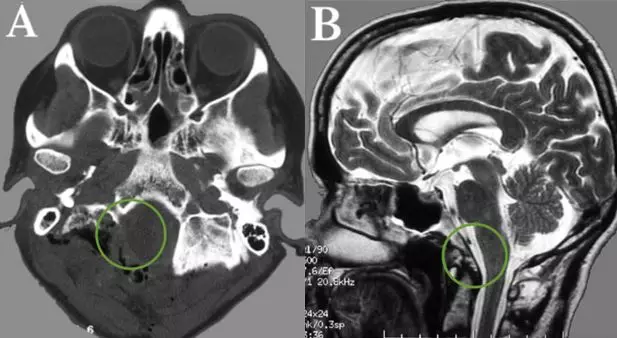

术后CT和MR,显示肿瘤及其被肿瘤侵犯的骨质都切除,肿瘤全切,Simpson一级切除。

术后Belle没有新发神经功能缺损,在术后第二天开始肢体活动,进行康复。虽然仍有轻微的颈部疼痛,但是很快就好转、消失。幸运的是,没有出现任何相关手术并发症,特别是没有脑脊液漏出或脊柱不稳定。术后计算机断层扫描(CT)和磁共振成像(MRI)分别显示了部分骨切除和肿瘤全切,术后伤口美观,也没有剃除全部头发。由于肿瘤全切,Belle未行放化疗,术后12年未见复发。